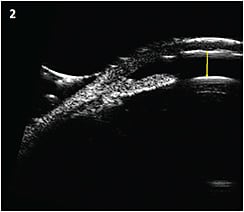

OCT and UBM imaging of the anterior chamber angle represent a major advance in our ability to understand the underlying pathophysiology of angle closure and to help properly diagnose and classify difficult cases such as plateau iris. In general, OCT imaging (Figure 1, page 59) allows visualization of the structures of the anterior chamber angle and allows quantification of various structural features of the angle. Those capabilities make this technology a powerful tool for research. I believe it is also helpful for demonstrating the anterior chamber angle anatomy for clinicians not proficient with gonioscopy.

Figure 1: Anterior segment OCT image of an eye with a narrow angle.

COURTESY ROBERT M. FELDMAN, MD